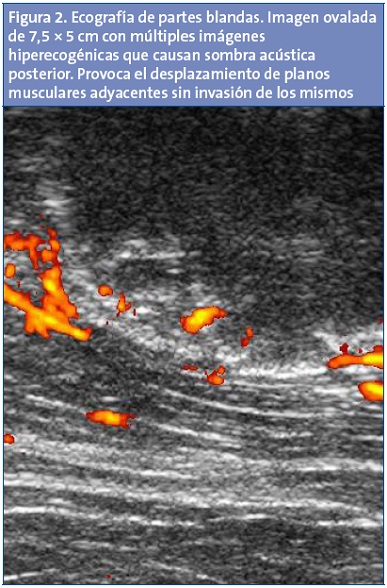

Ante los hallazgos clínicos se solicita radiografía simple del fémur izquierdo (Fig. 1) que evidencia una masa calcificada. Posteriormente se solicita ecografía del muslo (Fig. 2), que pone de manifiesto una imagen oval con múltiples imágenes hiperecogénicas en su interior que provocan sombras acústicas posteriores, lo que no sugiere un diagnóstico definitivo. Para concretar el diagnóstico se solicita una tomografía computarizada (TC) (Fig. 3), que pone de manifiesto una masa calcificada que no engloba estructuras neuromusculares, de características aparentemente benignas, pero que no permite descartar que se trate de un condroma de partes blandas.

La ecografía es una técnica de imagen inocua y útil para valorar lesiones de partes blandas, aunque depende mucho de la experiencia del explorador. Las imágenes que aporta indican con frecuencia infiltración de la grasa subcutánea y del músculo, lo cual sugiere malignidad. El osteosarcoma en fase inicial es difícil diferenciarlo de la miositis, pero las líneas hiperecogénicas con sombra acústica posterior sugieren MOT aunque estas no aparecen hasta las 2-3 semanas de evolución.